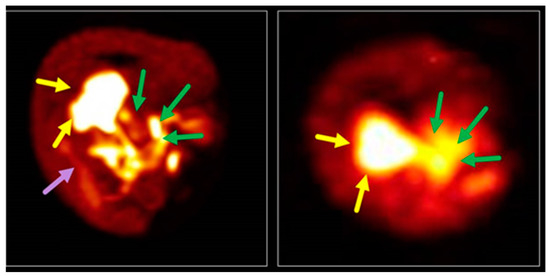

- Aparici, C.M.; Behr, S.C.; Seo, Y.; Kelley, R.K.; Corvera, C.; Gao, K.T.; Aggarwal, R.; Evans, M.J. Imaging hepatocellular carcinoma with 68Ga-citrate PET: First clinical experience. Mol. Imaging 2017, 16, 1–4. [Google Scholar] [CrossRef]